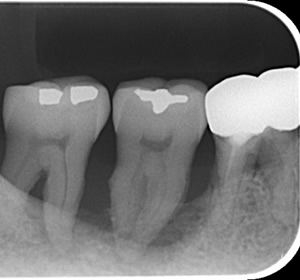

30代の患者さんで、「左下の奥歯が痛くて噛めない」ということで来院されました。

左下の一番奥の歯に進行したむし歯を認め、レントゲン写真を撮影すると、歯冠だけでなく、歯根の1/2まで進行しておりました。歯根が分岐している所まで歯が溶けてしまっています。

歯根がこのような状態なってしまうと、被せものを装着して噛めるようにすることはできませんので、抜歯せざるをえませんでした。